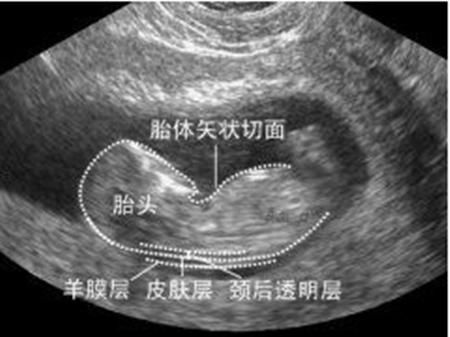

NT是指胎儿颈背部皮肤层与筋膜层之间最大厚度。仅仅在胎儿10-14周才会存在,NT越厚的胎儿,代表胎儿患染色体疾病以及心血管畸形概率越低。NT ≥2.5mm视为异常。

NT测量方法